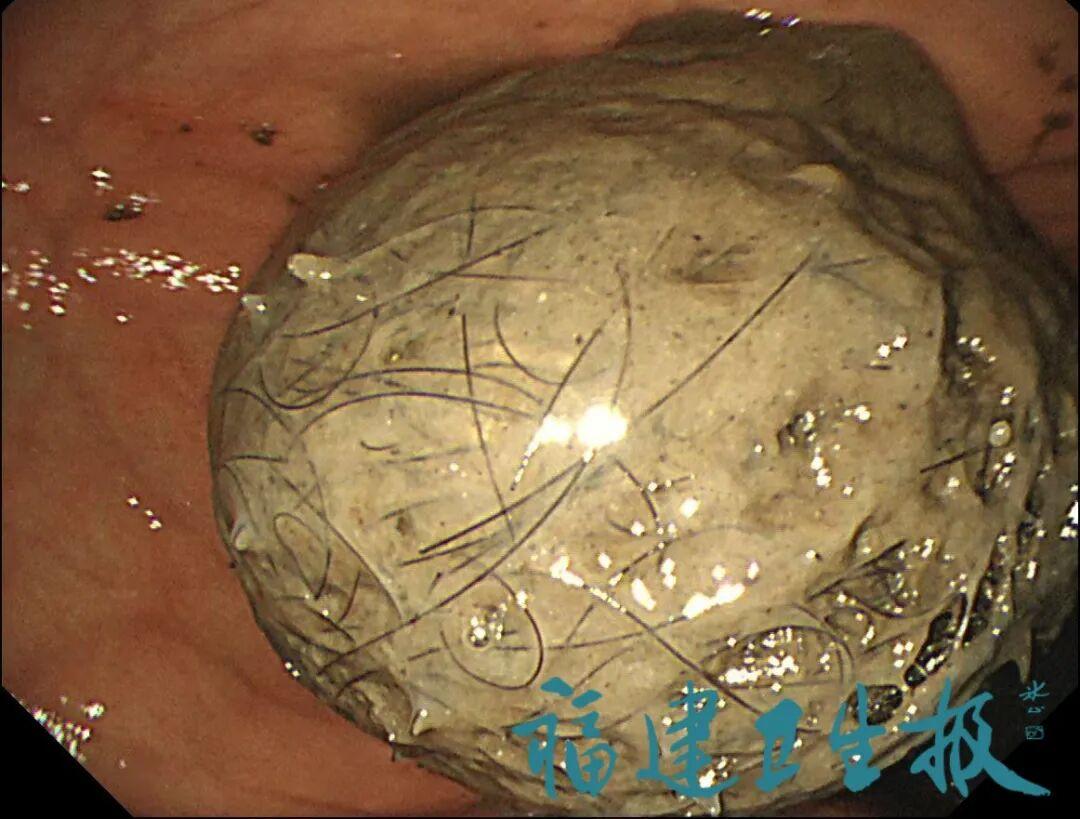

结果出来时,医生都惊呆了:小可的胃里,塞满了成团的头发,几乎占了胃容量的四分之三!大量不能消化的物质,在胃酸的作用下发生变性,并与食物及其他物质结合形成团块,慢慢变成坚硬的“胃石”。

为了避免用手术方式去除头发团,陈攸涛先让小可喝可乐软化“胃石”,再通过胃镜辅助取出头发,整个过程花了十几个小时,清理出的头发装了两大盆。